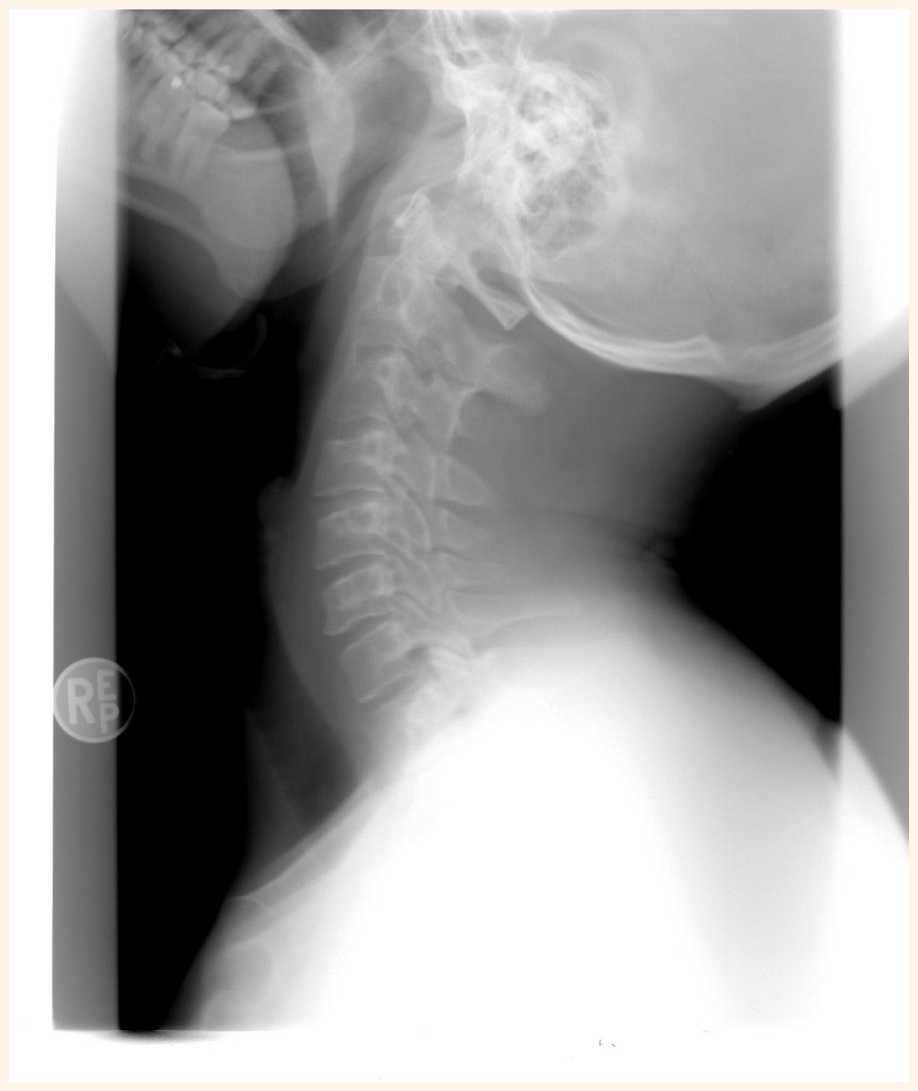

- X-ray(엑스레이): 경추의 정렬 상태와 퇴행성 변화를 확인하는 데 유용합니다.